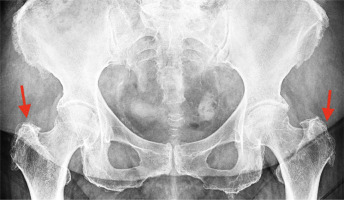

Fig. 2

Greater trochanter pain syndrome in standing pelvic X-ray (indicated with red arrows) – uneven outline of the greater trochanter, visible calcifications and osteophytes on the right and left sides.